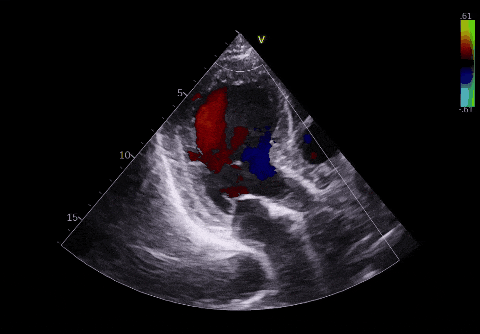

▲术前超声

左心室射血分数 (LVEF):这是衡量心脏“泵血功能”的核心指标。正常人的数值通常在 50%-70%。